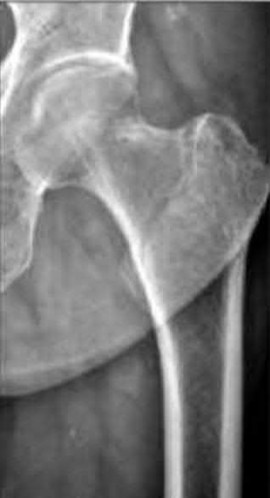

A 12-year-old obese boy presents with vague left thigh and knee pain. He is diagnosed with a Slipped Capital Femoral Epiphysis (SCFE) as seen in similar clinical scenarios.

During percutaneous in-situ fixation, unrecognized penetration of the guide wire into the hip joint occurs. What is the most likely specific complication resulting from this technical error?

Explanation

Chondrolysis is a severe complication of SCFE characterized by rapid destruction of the articular cartilage. While it can occur idiopathically, its most established iatrogenic cause is unrecognized intra-articular hardware penetration. The 'approach-withdraw' fluoroscopic technique is required during pinning to assure pins are entirely intraosseous. Avascular necrosis (AVN) is usually due to damage to the epiphyseal blood supply (retinacular vessels) secondary to the initial displacement, forceful closed reduction, or posterosuperior pin placement.